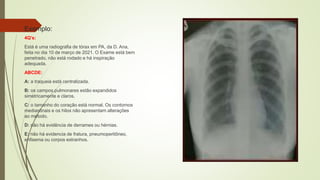

Exemplo:

4Q’s:

Está é uma radiografia de tórax em PA, da D. Ana,

feita no dia 10 de março de 2021. O Exame está bem

penetrado, não está rodado e há inspiração

adequada.

ABCDE:

A: a traqueia está centralizada.

B: os campos pulmonares estão expandidos

simetricamente e claros.

C: o tamanho do coração está normal. Os contornos

mediastinais e os hilos não apresentam alterações

ao método.

D: não há evidência de derrames ou hérnias.

E: não há evidencia de fratura, pneumoperitôneo,

enfisema ou corpos estranhos.